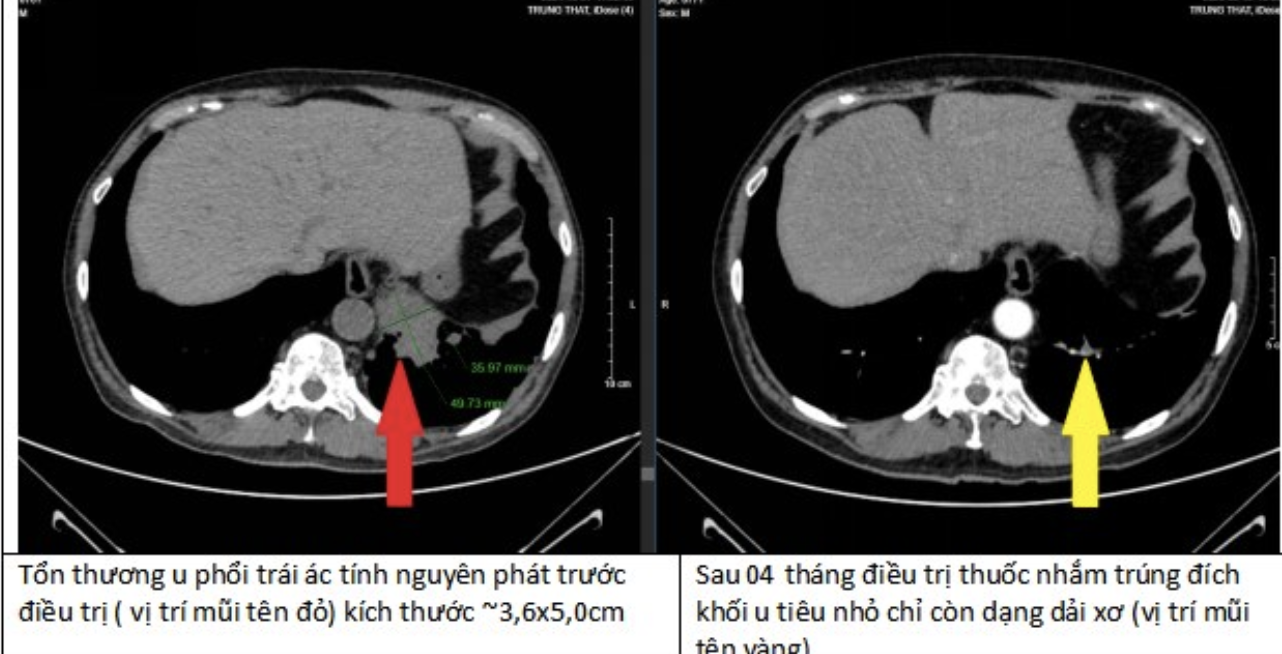

Khối u tại phổi biến mất 90% nhờ tuân thủ điều trị

Sau 4 tháng điều trị, các khối u tại phổi, não, xương của bệnh nhân đều thu nhỏ lại. Đặc biệt tại phổi, khối u đã biến mất tới 90%. Đây là một kết quả kinh ngạc, tạo ra kỳ tích cho bệnh nhân.

“Bằng việc tuân thủ điều trị theo đúng phác đồ, bệnh nhân có kết quả hoàn toàn bất ngờ “thần kỳ” sau 4 tháng điều trị”, bác sĩ Duy Anh chia sẻ.